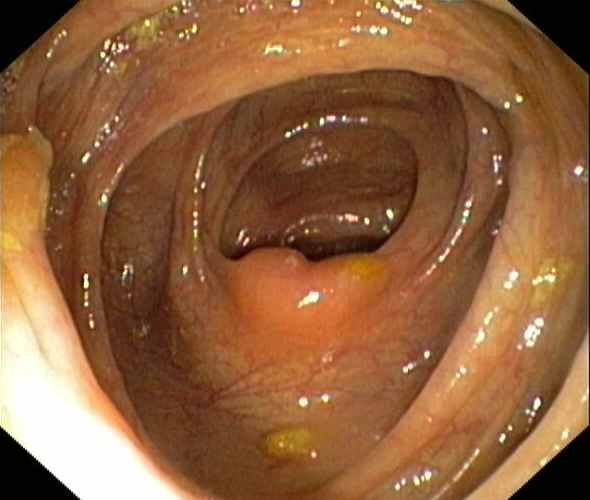

Ileocaecal valve